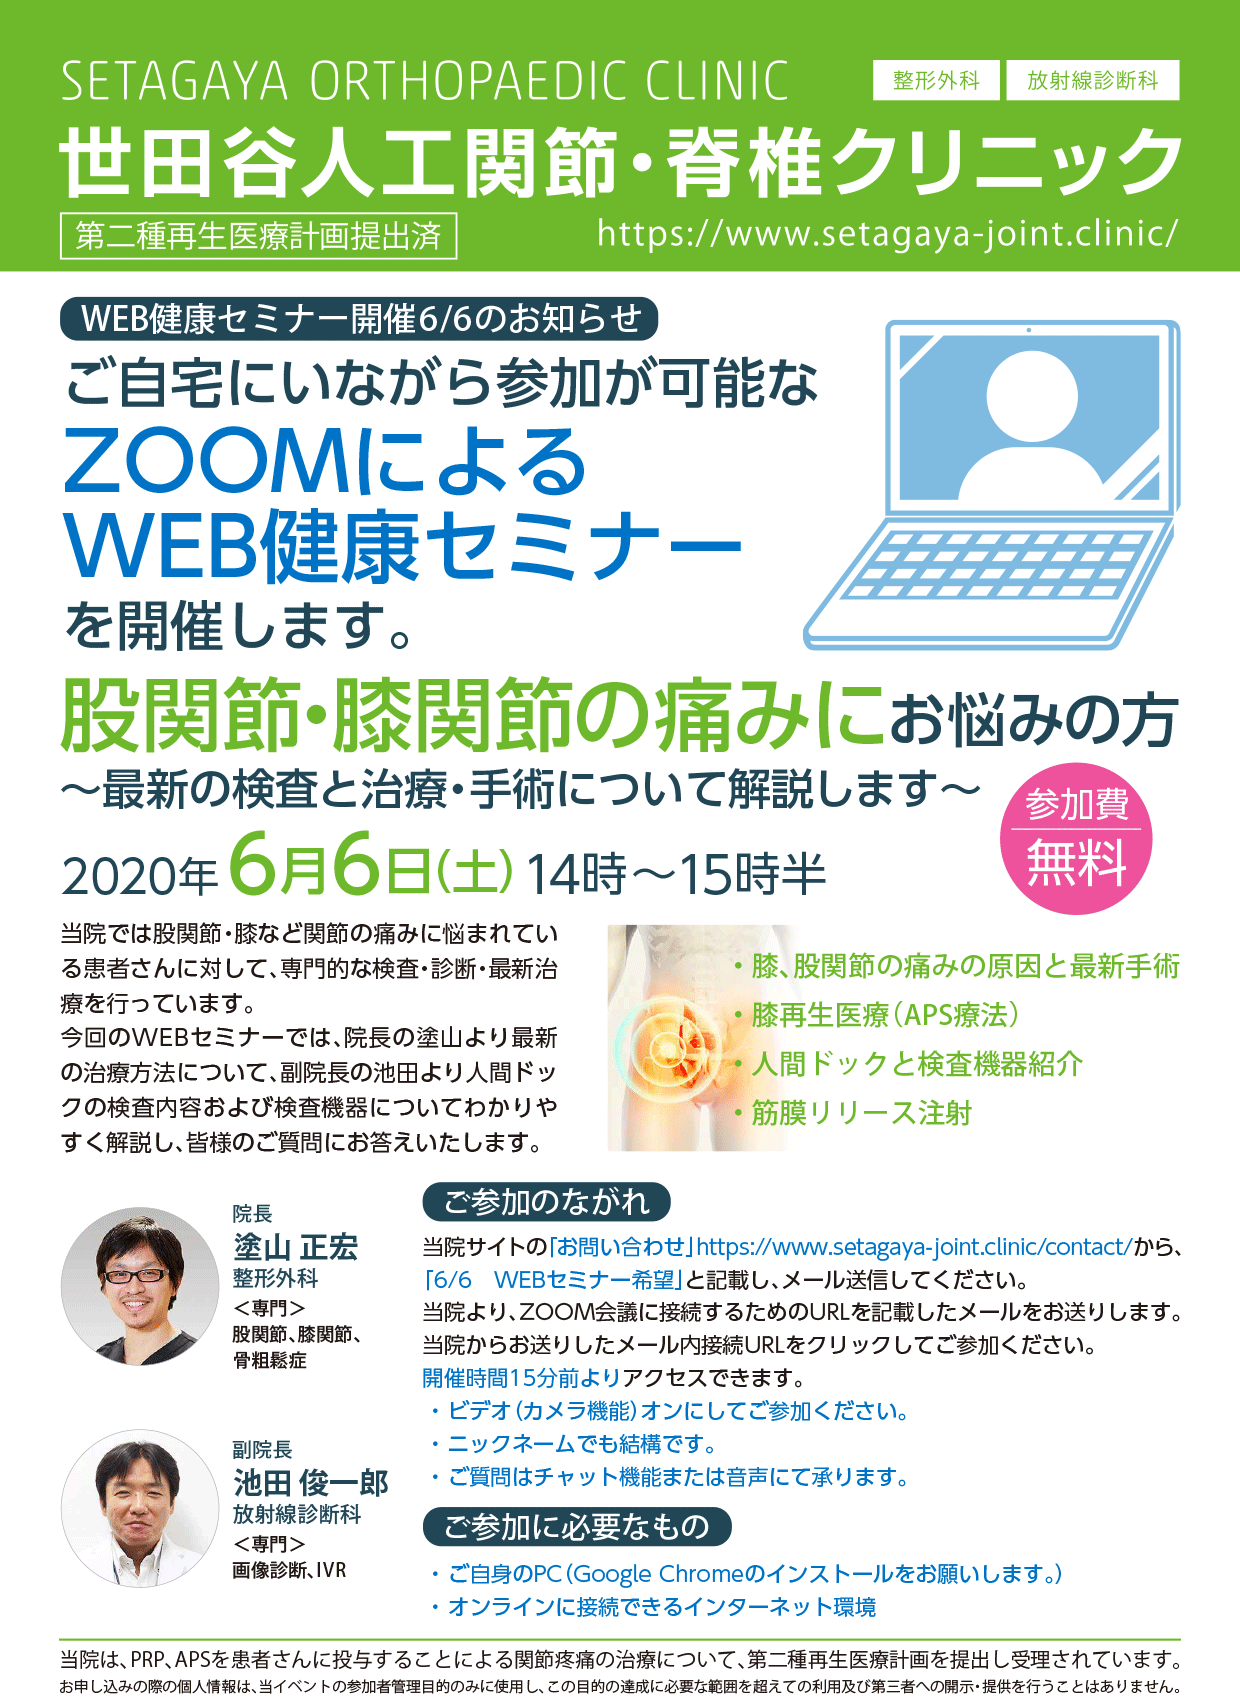

ここでお知らせです!

6月6日に初のWebセミナーを開催します!

初の試みなんでどうなるかわかりませんが・・・(汗)

みなさんの御参加をお待ちしております!

【ご参加の流れ】

お申込みはホームページより承ります。

お問い合わせフォームに移動していただき、

<お問い合わせ内容>に「6月6日WEBセミナー参加希望」とご記入ください。

当院より、ZOOM会議に接続するためのURLを記載したメールをお送りします。

当日は、当院からお送りしたメール内接続URLをクリックしてご参加ください。

開催時間15分前(13時45分)よりアクセスできます。

- ビデオ(カメラ機能)オンにしてご参加ください。

- ご質問は音声の他、チャット機能でも承ります。